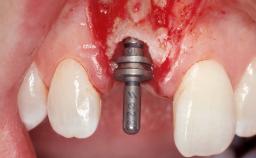

| Placement Protocol | Immediate implant placement |

| Socket Morphology | Single-root socket |

| Socket Integrity | Damage to one or more bone walls |